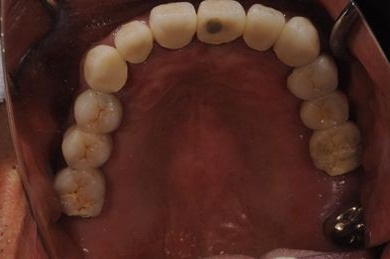

インプラントの症例写真 IMPLANT

骨再生インプラント治療

| 治療方針 | 右上奥はソケットリフトにて上顎洞拳上してインプラント埋入を可能にし、上顎前歯部は骨再生法によりインプラント治療を行う。その他、補綴により口腔内全体の機能的審美的回復を行う。 | ||||||||||||||||||||||||||||||||

| 治療内容 | インプラント8本(GBR、ソケットリフト)、ハイブリッドセラミッククラウン17本(セラミック用土台5本) | ||||||||||||||||||||||||||||||||